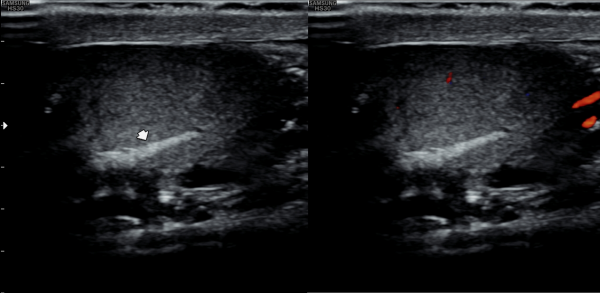

첫 내원 당일 측면 경직장 전립선 초음파 검사상 사정관 입구의 결석과 폐쇄로 사정관 낭종이 관찰되고 사정관에 탈락된 상피세포가 쌓여 사정관이 막히고 있으며 요도 협착등 배뇨 장애로 방관내 조직의 이상 증식이 관찰되는 초음파 사진 입니다.

On the first day of the visit, a lateral transrectal prostate ultrasound revealed stones and obstruction at the entrance of the ejaculatory ducts, leading to ejaculatory duct cysts. Detached epithelial cell debris was observed accumulating and blocking the ducts. In addition, abnormal tissue proliferation within the bladder was noted, likely due to urethral stricture and associated voiding dysfunction.

내원 당일 고환의 초음파 사진상 사정관의 결석과 섬유화로 정관의 순환 장애를 일으켜 좌우 고환의 섬유화가 생기고 있는 고환 초음파 사진입니다.

This is a scrotal ultrasound image taken on the day of the initial visit, showing fibrosis in both testes caused by obstructed circulation in the vas deferens due to calcifications and fibrosis of the ejaculatory ducts.